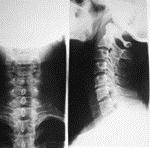

问题 病历摘要: 患者男性,67岁,因颈肩痛、臂痛併四肢乏力3年入院。体检:神清,颈项僵硬,双上肢、上臂外侧、三角肌区皮肤感觉减退,三角肌肌力Ⅲ级,肱二头肌反射亢进,肱三头肌反射亢进,双上肢霍夫曼氏征(+),双下肢皮肤感觉正常,肌力正常,膝反射、跟腱反射亢进,髌阵挛(+),踝阵挛(+)。 根据以上资料,最有可能的诊断是: 提示:X线片、MRI见图:

选项 A、椎间盘钙化 B、脊髓型颈椎病 C、交感型颈椎病 D、神经根型颈椎病 E、食管受压型颈椎病 F、后纵韧带骨化 G、椎动脉型颈椎病 H、混合型颈椎病

答案 B